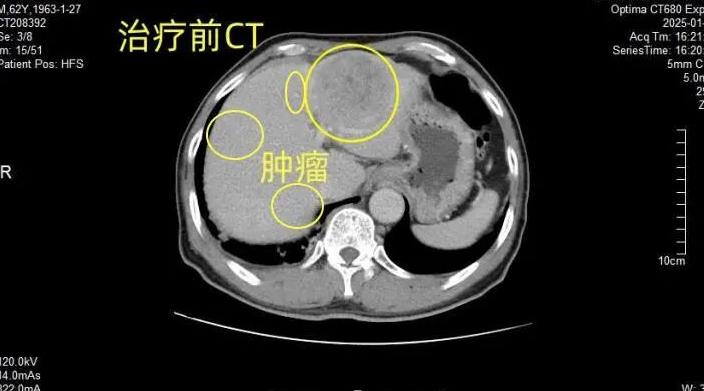

该患者初诊时因肿瘤巨大、存在血管侵犯或多发转移,被判定为肝癌晚期,失去直接手术切除的机会。为挽救患者生命,医院立即启动多学科协作模式,由肝胆外科牵头,联合超声科、肿瘤科、影像科共同制定治疗方案。

团队为患者采用靶向药物、免疫治疗与介入治疗(TACE)相结合的转化治疗方案。经过 7 个月系统治疗,患者肿瘤状态成功从 “不可切除” 转化为 “可切除”。随后,肝胆外科在超声科刘青林主任团队的技术支持下,为患者实施肝叶切除术,并同步开展术中超声造影、术中射频消融术,精准清除肿瘤病灶。整场手术历时 2 小时,过程顺利。